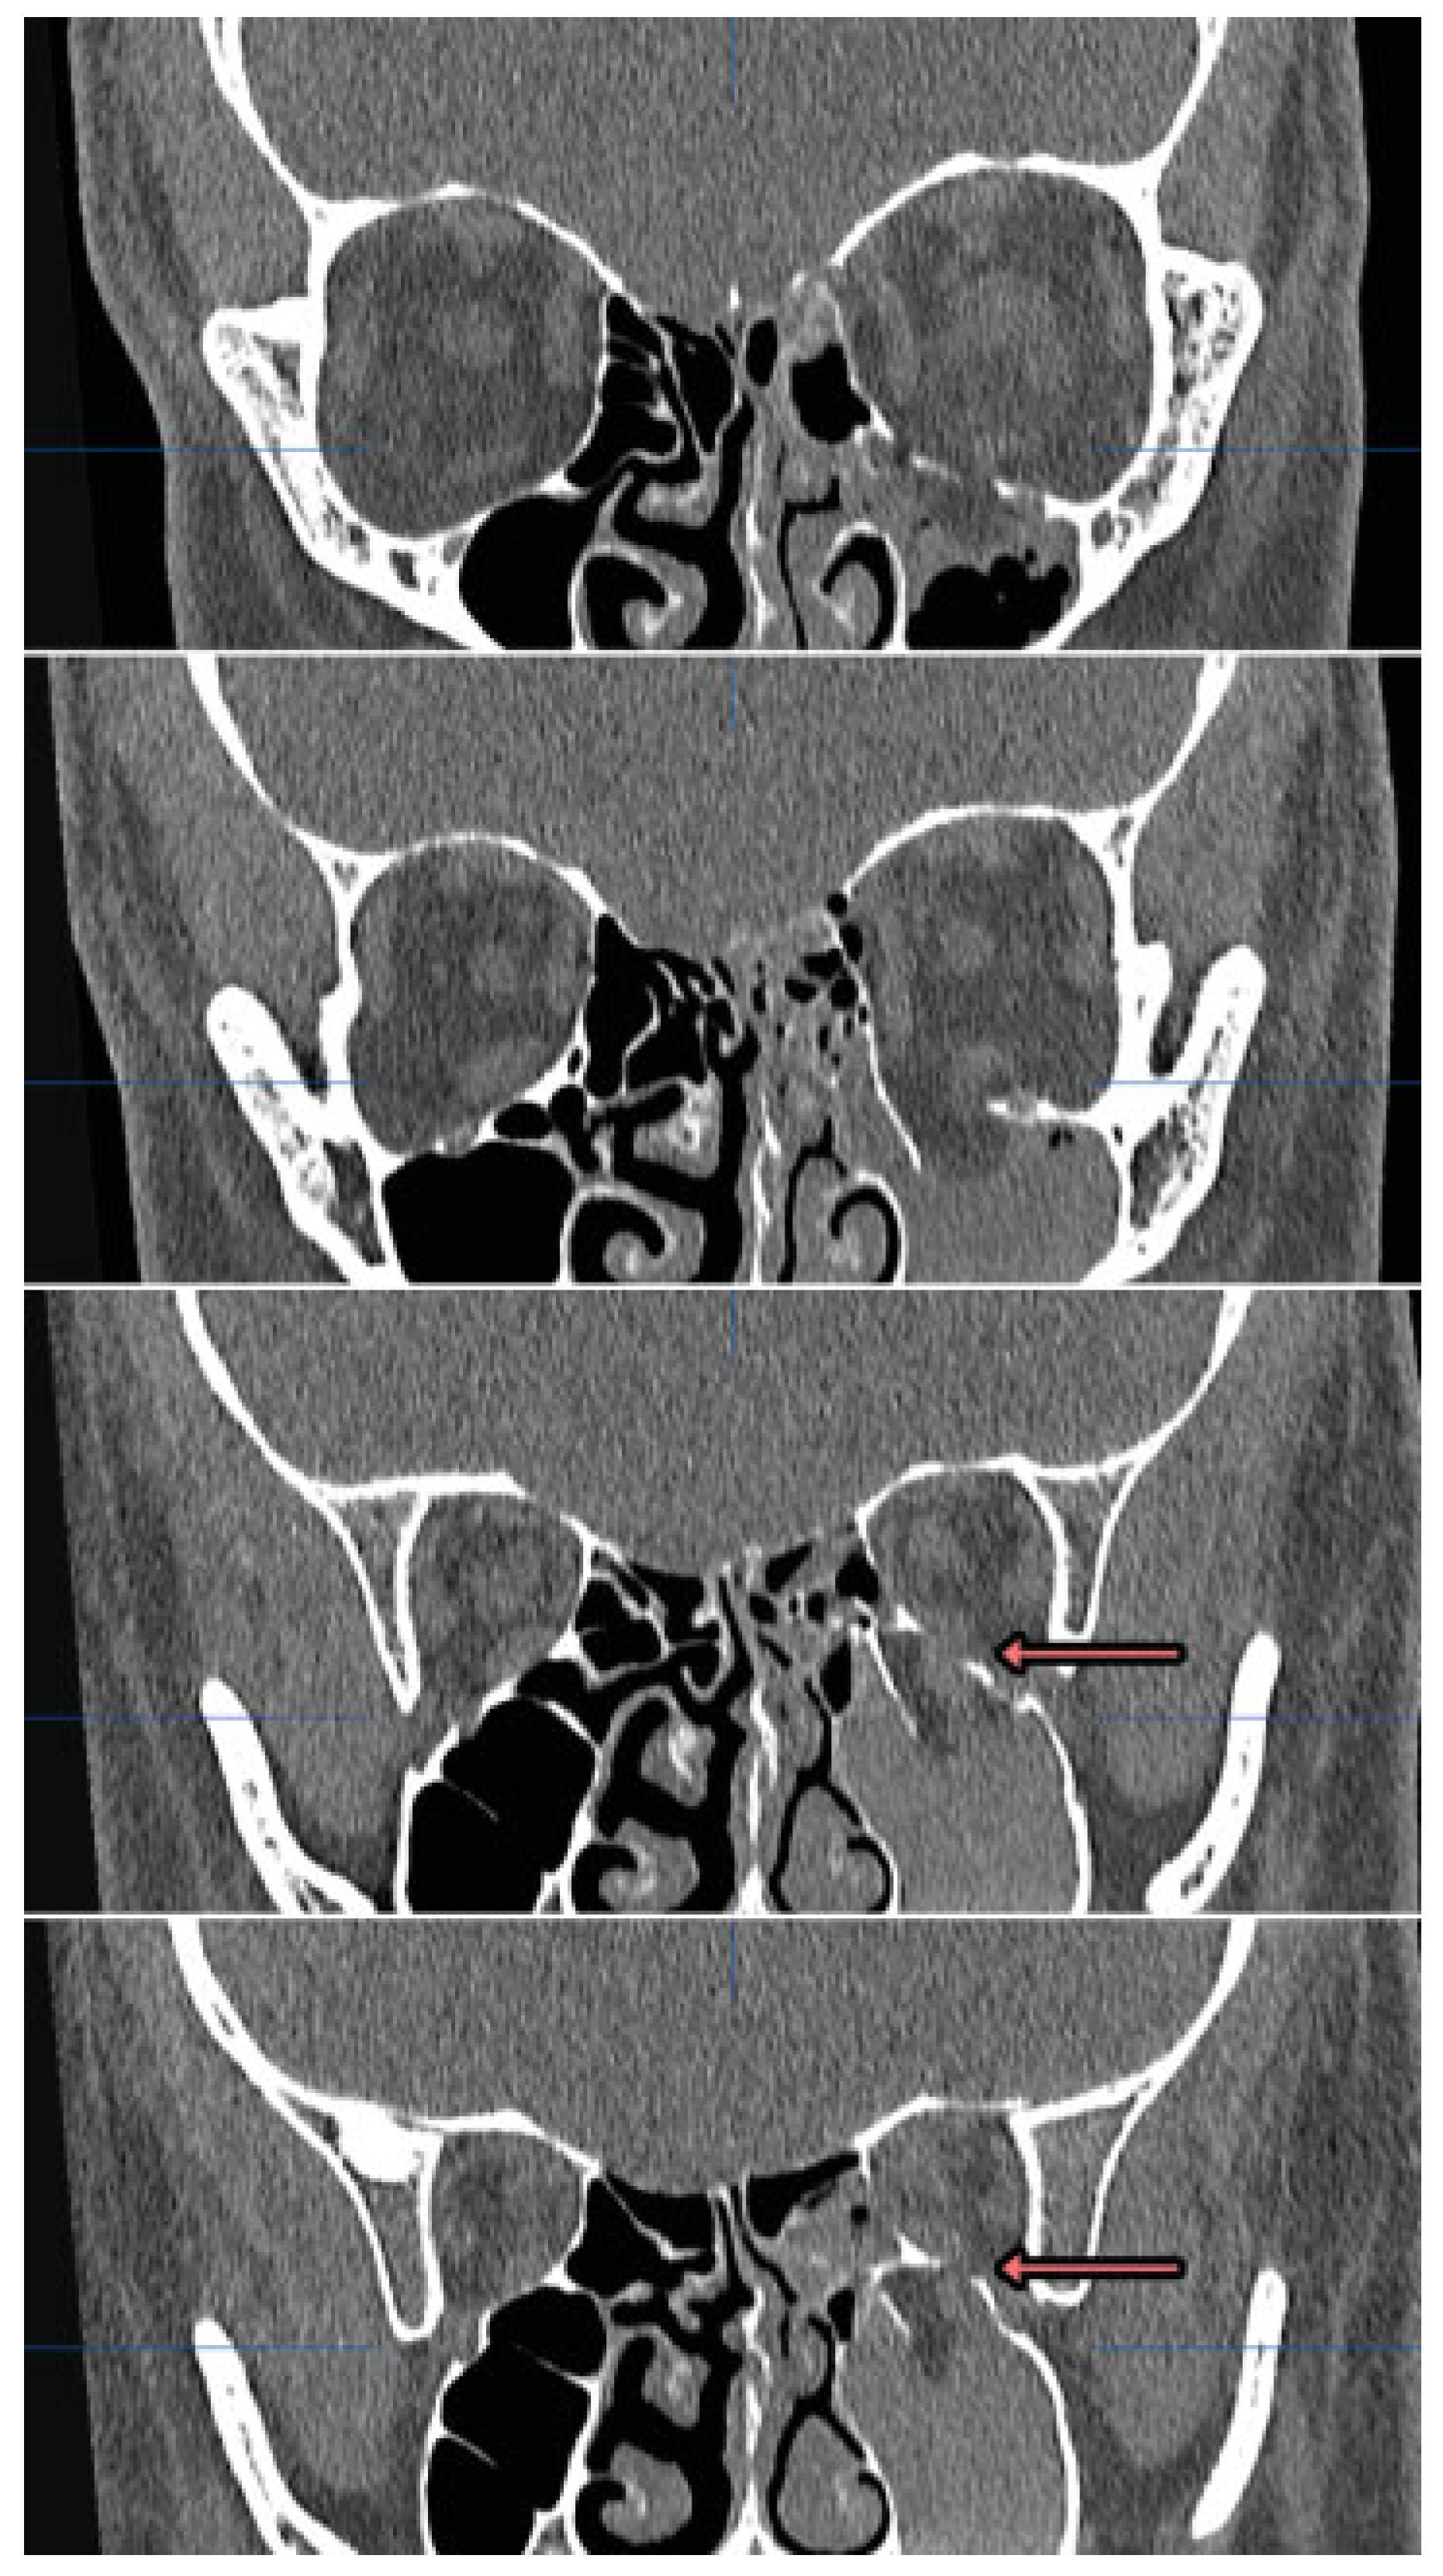

Noncontrast orbital CT scan demonstrated a comminuted left orbital floor fracture and an associated minimally displaced fracture of the left lamina papyracea and nasal bones. The shape of the inferior rectus muscle was distorted vertically and it appeared to be partially entrapped in the orbital floor fracture (Figure 2).

In this patient, a large orbital floor and medial wall fracture was present. Although the anterior portion was classically displaced, the posterior portion of the floor was atypically nondisplaced. Consequently, posterior portions of the left inferior rectus muscle and sheath became caught between two nondisplaced bone fragments (Figure 2, red arrows) and clinically evident extraocular muscle entrapment was seen. While entrapment through a nondisplaced fracture is rare in adults, this should be differentiated from herniation of orbital tissue in a displaced fracture, which is common. In herniation, there is no strangulation of muscle tissue and the risks of muscle damage, necrosis, or the OCR are lower. Occasionally when muscle or perimuscular tissue is herniated, limitation of gaze can be manifest clinically and a distortion of the shape of the inferior rectus can be observed radiographically [6] (Figure 7).

Figure 2. Computed tomography of a left partially displaced orbital floor fracture and nondisplaced medial wall fracture with prominent her- niation of orbital fat through the defect centrally and posterior entrapment of the inferior rectus muscle in nondisplaced fracture elements (red arrows).